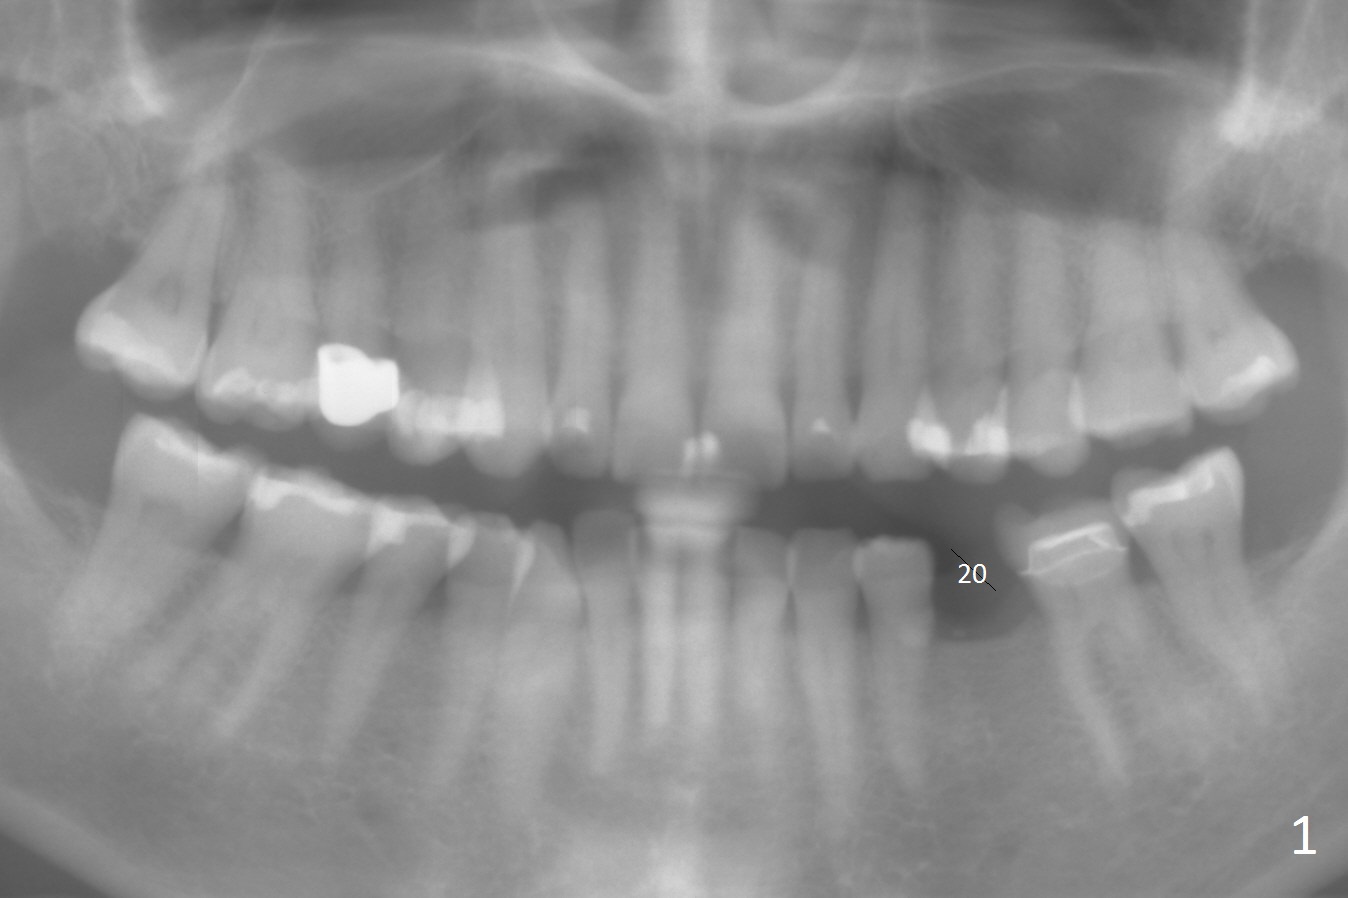

A 54-year-old woman has good oral hygiene.  Panoramic X-ray shows generalized long roots, which suggest bruxism (Fig.1).  Since the bone height is sufficient, a long implant will be placed, probably 4x13 mm (Fig.2).  Take photos of the edentulous space, concentrating on the ridge top.  Flap surgery will be performed.  Crestal bone is going to be reduced if the ridge is narrow.  PA is taken after 1.6 mm drill for 11 mm.  If the trajectory is correct, a 3.3 mm Magic Drill is to be used (13 mm stopper, after Marking bur), followed by 4x11 mm dummy implant.  If the bone is dense, a final drill will be used for 14 mm before placement of the definitive implant.  The harvested autogenous bone will be placed around a pair abutment to increase the buccolingual width.  Take postop photos to show the ridge augmentation.